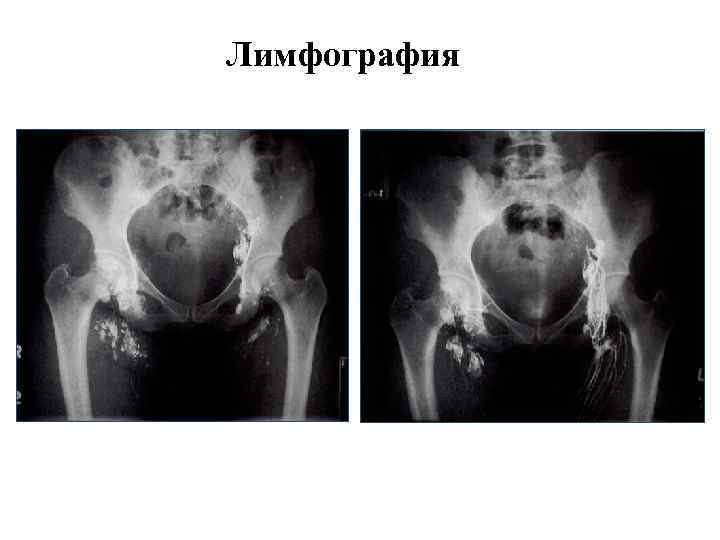

Лимфография

Лимфография